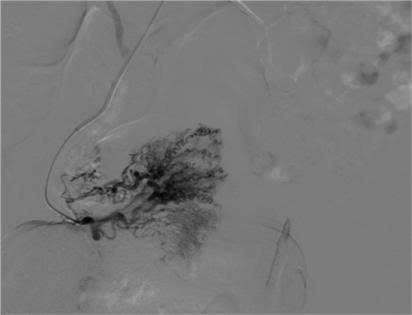

Bệnh nhân ngay lập tức được chuyển sang hội chẩn tại Trung tâm Can thiệp mạch – Bệnh viện Việt Đức. Kết quả chụp mạch số hóa xóa nền (DSA) xác nhận chẩn đoán ban đầu chính xác, đồng thời tiến hành nút mạch tại các vùng mạch máu tổn thương.

ra-mau-1.jpg

Hình ảnh búi mạch bất thường trên DSA - Ảnh BVCC